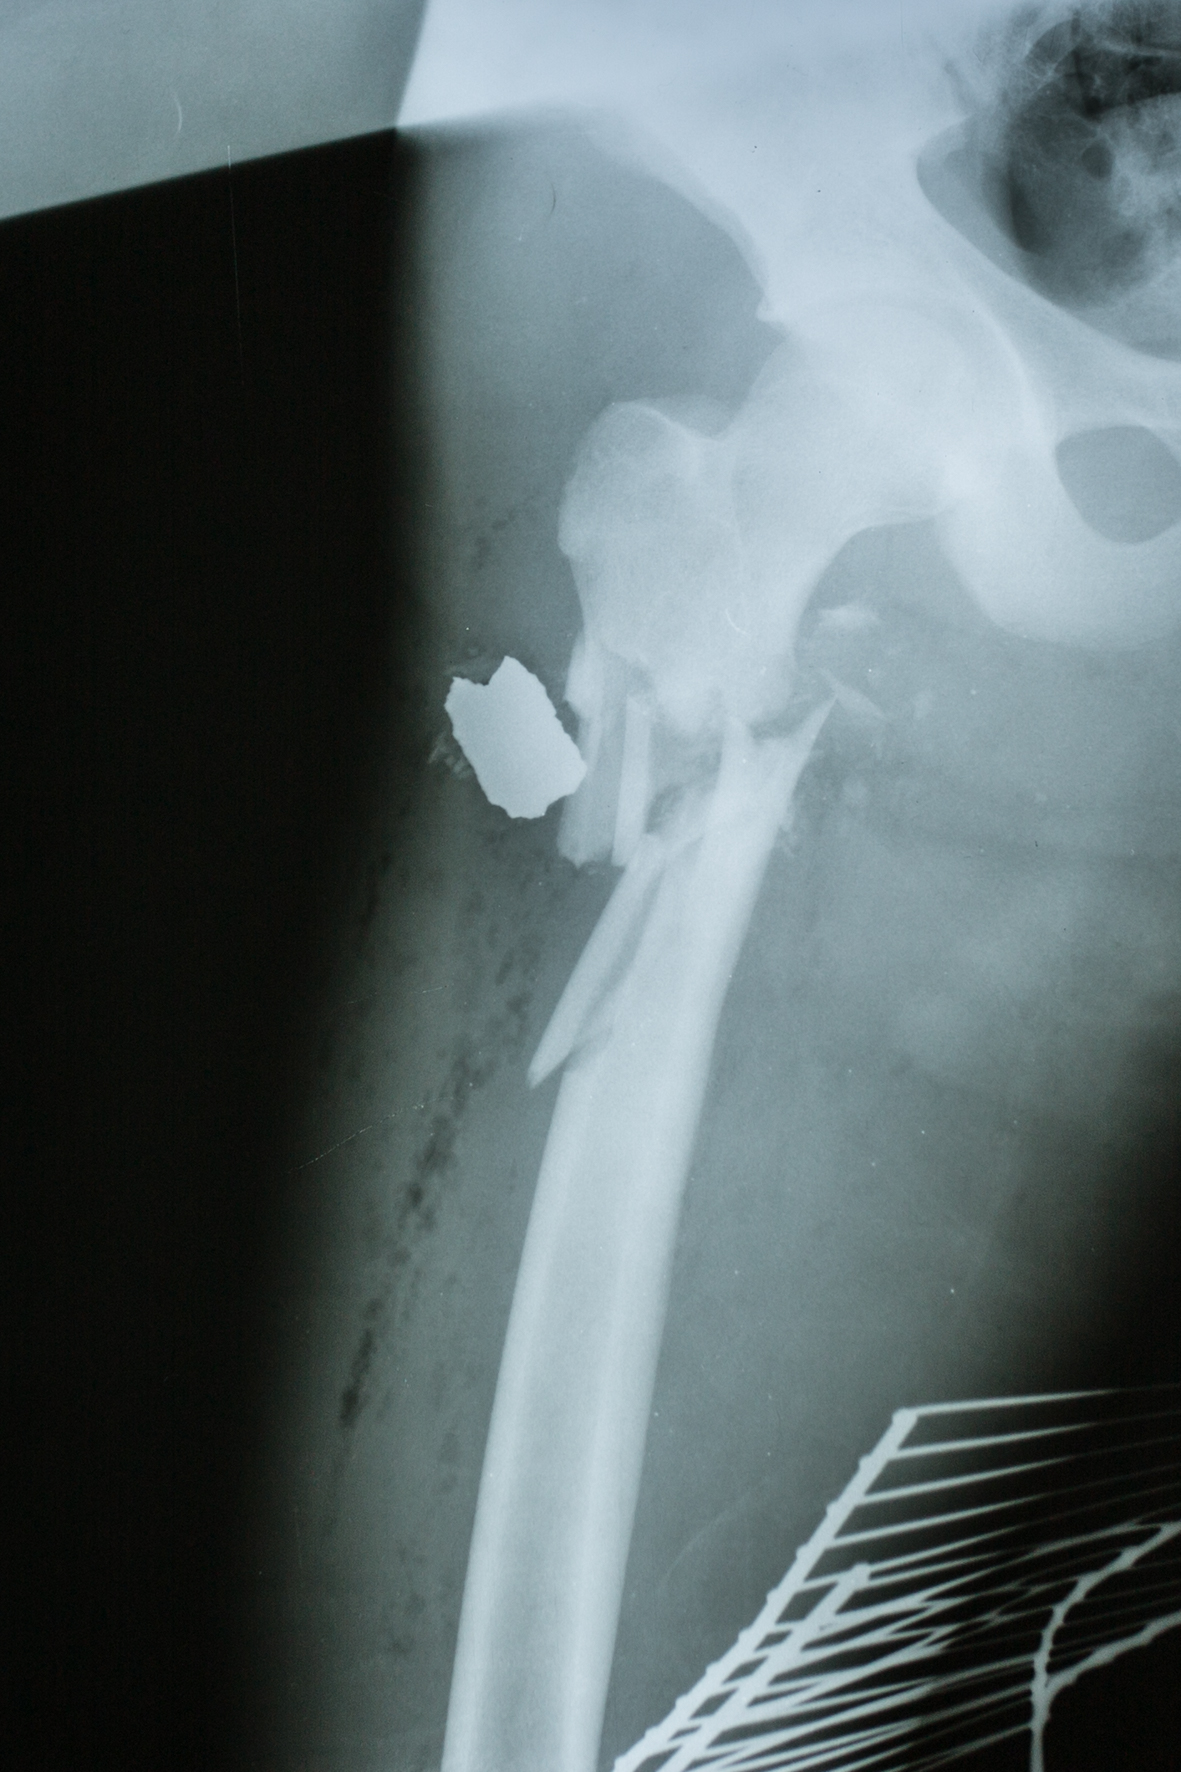

War is one hour away.

Surgical operations in Erbil and Shekhan / Iraq 2017 / for

ICRC